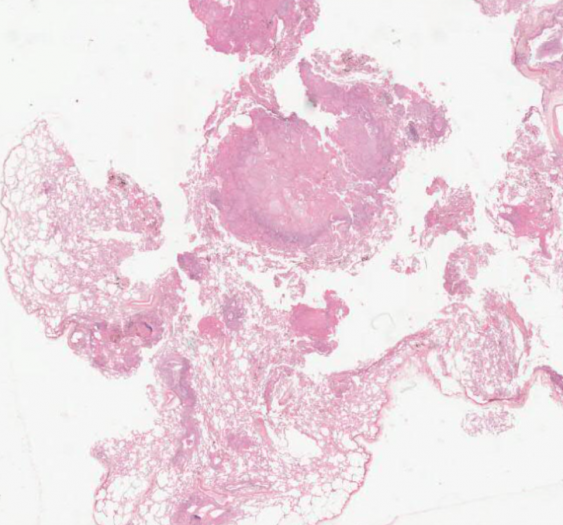

2、数字资源:划分有专门的数字资源模块,包含400多个精细的3D病理虚拟模型、700多个3D病理大体标本、50个手术入路解剖3D模型、400多张病理学数字切片、200多部临床 手术3D动画、30部病理学3D动画、100多部病理学数字切片微视频等资源,以震撼的视觉吸引力、丰富易读的知识点精彩呈现。